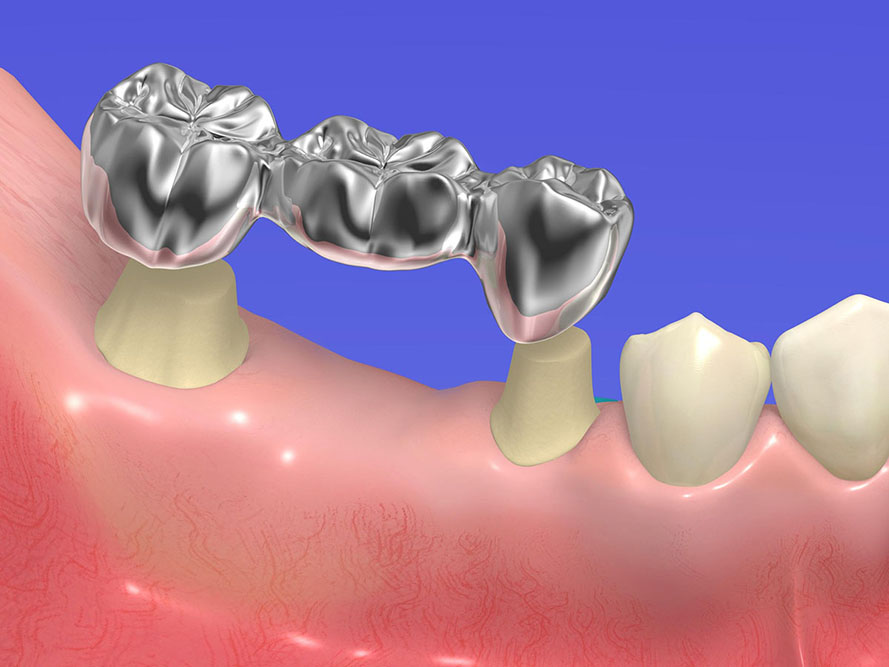

Bridges

In case of a tooth gap between 2 intact teeth, a bridge is used. The adjacent teeth are used as pillars. With bridges, even large gaps can be closed.